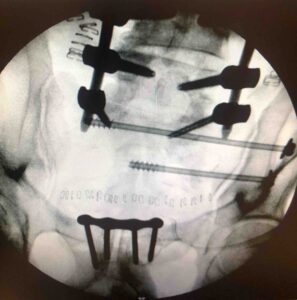

Εδώ, λοιπόν, έρχεται η χειρουργική χαμηλής παρεμβατικότητας, η οποία και σε αυτόν τον απαιτητικό τομέα επιτρέπει να χειρουργηθεί ο ασθενής άμεσα, την πρώτη κιόλας ημέρα. Η τεχνική αυτή δίνει τη δυνατότητα να σταθεροποιηθούν τα κατάγματά του και να ελεγχθεί κατά πόσο έχουν αναταχθεί (έχουν έρθει στη θέση τους τα παρεκτοπισμένα τμήματα οστού) με την τρισδιάστατη απεικόνιση κατά τη διάρκεια του χειρουργείου. Στηριζόμαστε στη χρήση πλοήγησης (navigation) και Ο-arm (εικόνα), εργαλεία που βοηθούν στην καλύτερη δυνατή αποκατάσταση του κατάγματος.